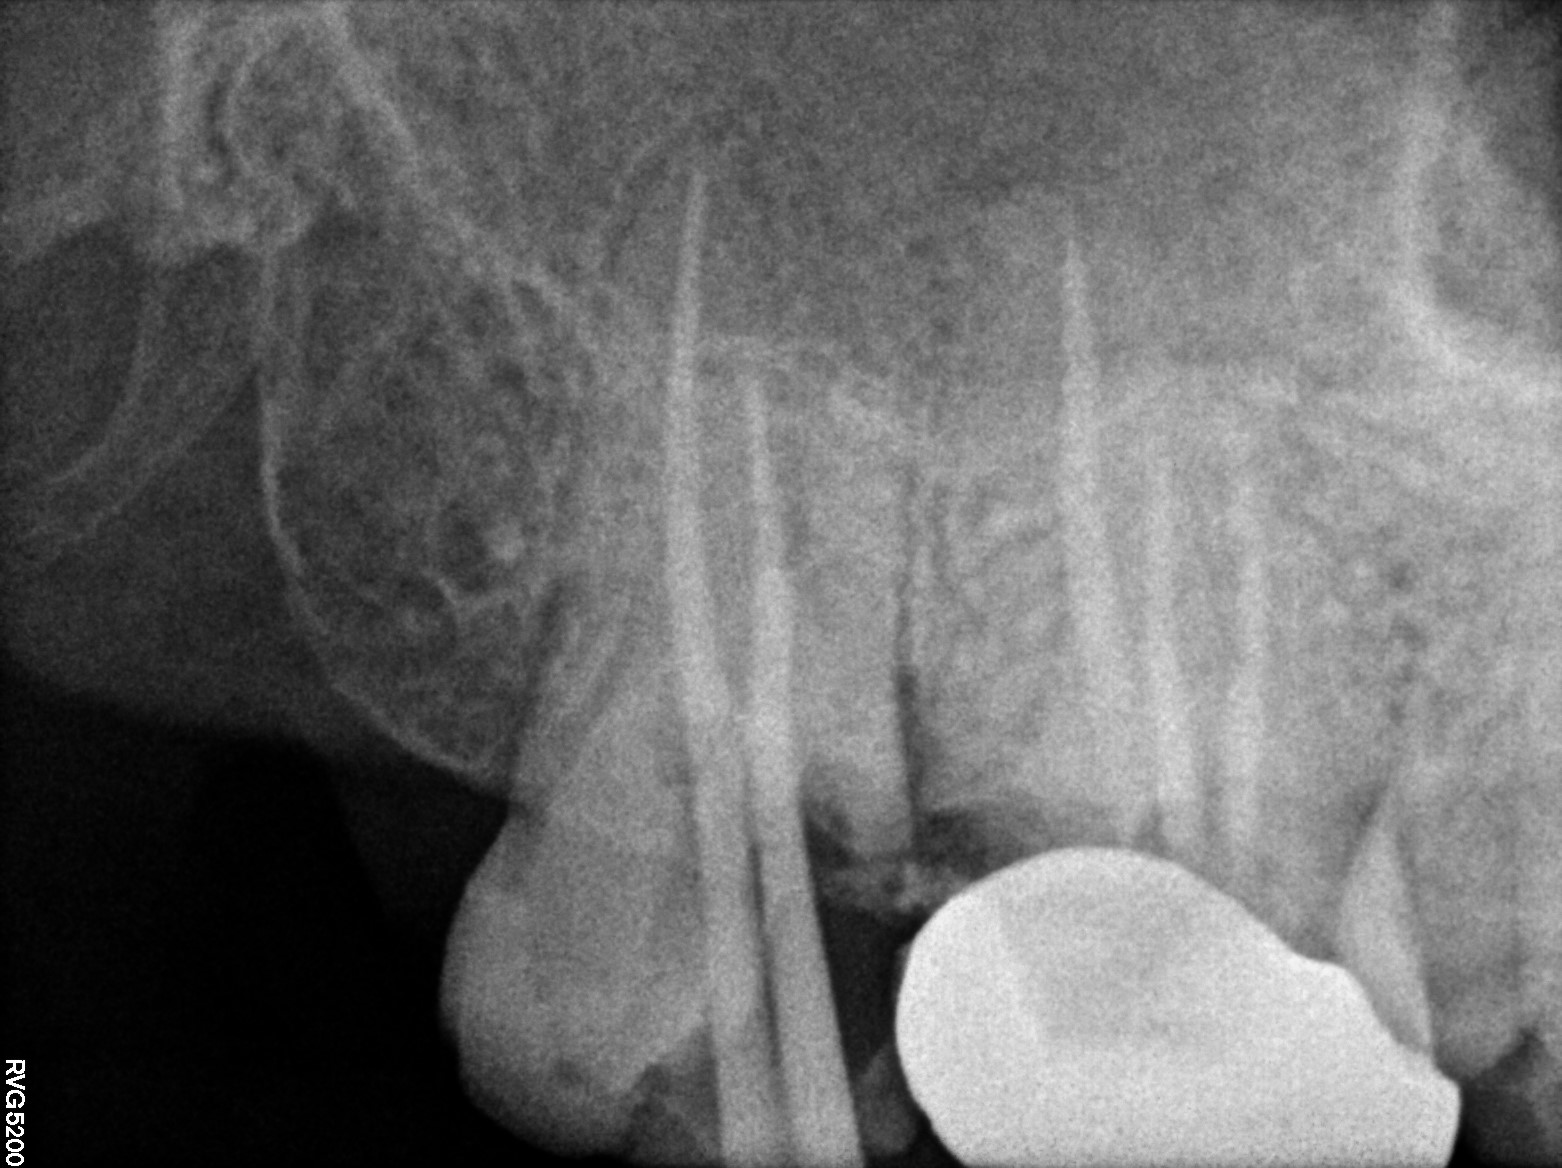

Dental Radiographs FHIR: DocumentReference · LOINC 24641-7

xray_1741331912.jpg

24641-7